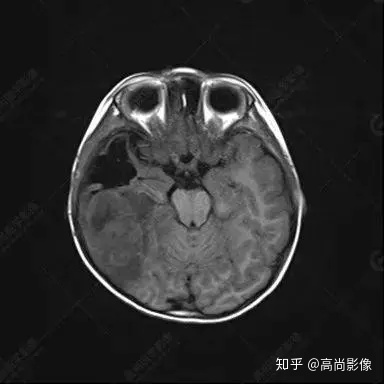

右側(cè)顳葉腫瘤切除術(shù)后(具體不詳):右側(cè)顳部骨質(zhì)不連續(xù)呈術(shù)后改變,右側(cè)顳葉術(shù)區(qū)見片狀長(zhǎng)T1長(zhǎng)T2信號(hào)影,F(xiàn)LAIR呈低信號(hào);術(shù)區(qū)后方右側(cè)顳枕葉見一巨大占位性病變影,邊界欠清,大小約6.2×5.8×4.3cm(前后×左右×上下),信號(hào)不均勻,T1WI呈等稍低信號(hào)間雜少許高信號(hào),T2WI呈高稍低混雜信號(hào),DWI示部分病灶彌散受限,相應(yīng)ADC圖減低,磁敏感序列見部分呈極低信號(hào),增強(qiáng)掃描可見明顯不均勻強(qiáng)化,鄰近硬腦膜及小腦幕增厚并明顯強(qiáng)化;另延髓右前方及右側(cè)橋小腦角區(qū)見一不規(guī)則形異常信號(hào)影,大小約3.2×1.3×3.7cm(左右×前后×上下),呈長(zhǎng)T1稍長(zhǎng)T2信號(hào),F(xiàn)LAIR呈等信號(hào),DWI未見受限,增強(qiáng)后明顯均勻強(qiáng)化,鄰近腦膜明顯強(qiáng)化。鄰近腦實(shí)質(zhì)及右側(cè)顳角明顯受壓;左側(cè)大腦半球未見局灶性信號(hào)異常,中線結(jié)構(gòu)稍左移。

右側(cè)顳葉腫瘤切除術(shù)后:現(xiàn)術(shù)區(qū)后方右側(cè)顳枕葉及延髓右前方占位,右側(cè)顳枕部硬腦膜及小腦幕明顯強(qiáng)化,結(jié)合既往影像資料,考慮為胚胎源性惡性腫瘤,如非典型畸胎樣/橫紋肌樣瘤(AT/RT)或原始神經(jīng)外胚層腫瘤(PNET)。